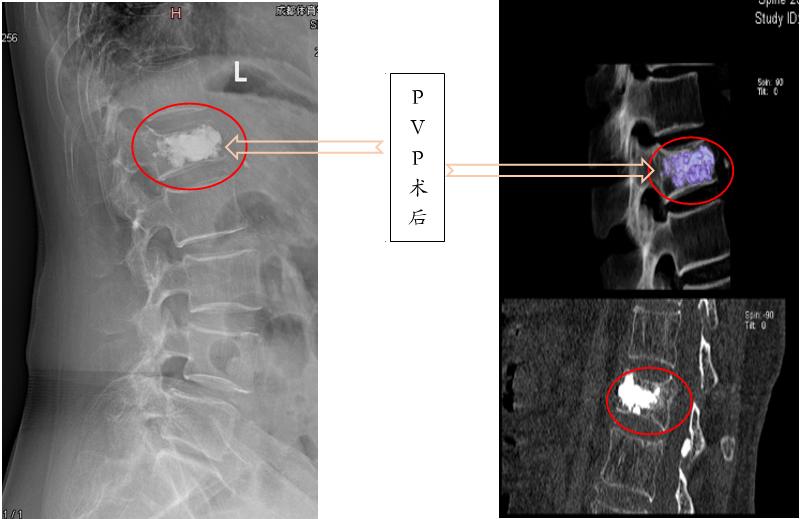

经皮椎体成形术(PVP) :通过向病变椎体内注入骨水泥达到强化椎体的技术。适用于非手术治疗无效、疼痛明显;不宜长时间卧床者;骨折不愈合或内部囊性病变、椎体坏死;能耐受手术者。